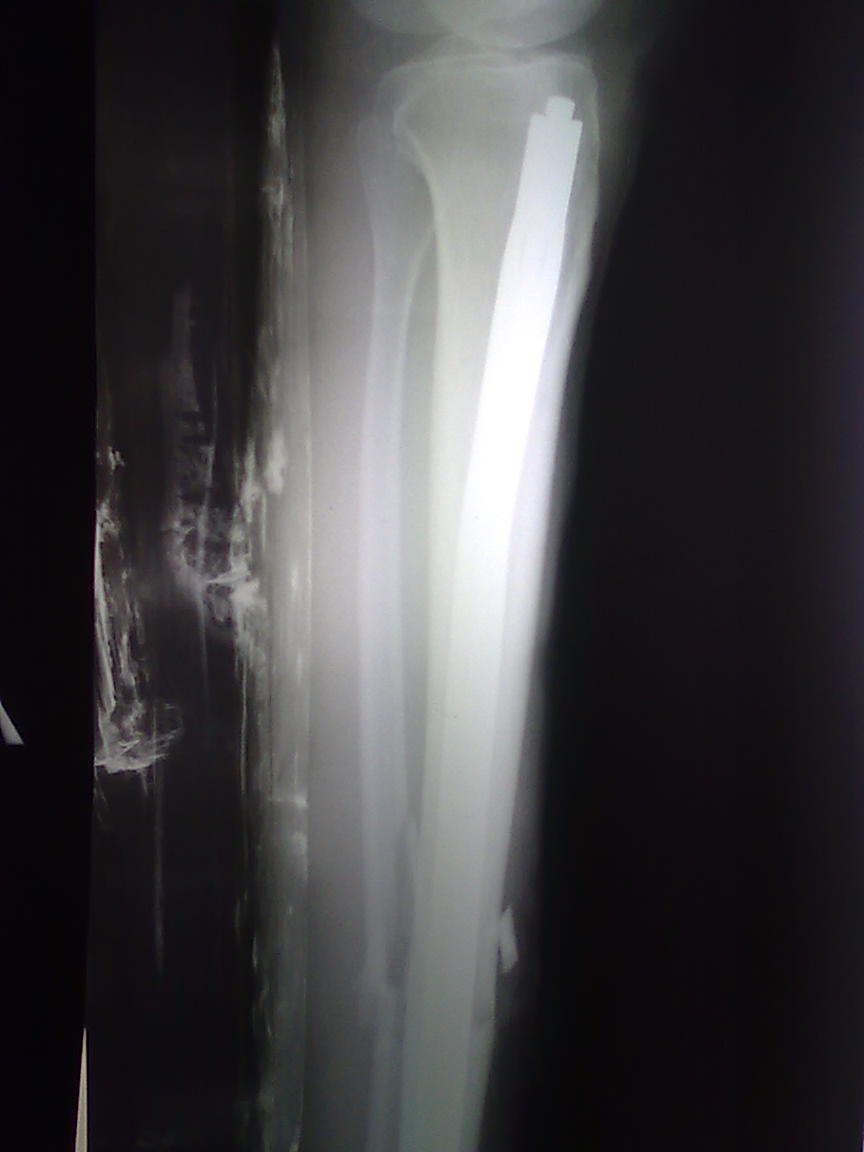

Добрый день, коллеги. Хочется поделится впечатлениями от установки гвоздя Fixion в большеберцовую кость по поводу попреченого перелома обеих костей голени в с/3.

Впечатление от конструкции в целом хорошее, но вопросы после установки остались. 1) Стоит ли подготавливать канал риммерами до установки гвоздя?2) Как правильно подобрать диаметр: у нас имелись гводи диаметром 8,5 мм и 10 мм. У пациентки диаметр самой узкой части кости 10 мм, самой широкой 15 мм. Коллеги-травматологи считали, что подготавливать канал риммерами не стоит, и гвоздь в данном случае стоит поставить диметром 8,5 мм. Мы же поставили гвоздь диметром 10 мм, и канал риммерами подготовили поочередно с 8 по 11. Поскольку опыт по установке гвоздя в нашем голроде незначительный, однозначно на данный вопрос ответить никто не мог3)На операции после нагнетения физ.р-ра в гвоздь до давления в 70 атм. произошло откалывание незначительного костного фрагмента проксимального отломка, вызванного по всей видимоcти давлением гвоздя изнутри канала. Вопрос в том, как этого можно избежать в дальнейшем. Итоговый результат операции нас вполне удовлетворил. Стабильность и адаптация хорошие.Спасибо.

Вы не показываете снимок, так что рассуждения несколько абстрактные. 8,5 мм расправляется до 13,5 мм, что выглядит вполне достаточно. Это

как раз и есть приятная особенность расширяемых гвоздей - рассверливать (не понимаю, чем лучше слово "римировать" или, того пуще, "рЕмировать") надо, только если перелом не очень близко от узкого истмуса. Правда, чем дальше от истмуса, тем более предпочтительны гвозди с винтами.

Такое случается и при неидеальном сопоставлении (кортекс одного отломка накладывается на другой), и при уже имевшихся продольных расщепах. Да и после рассверливания кортекс стал тоньше.